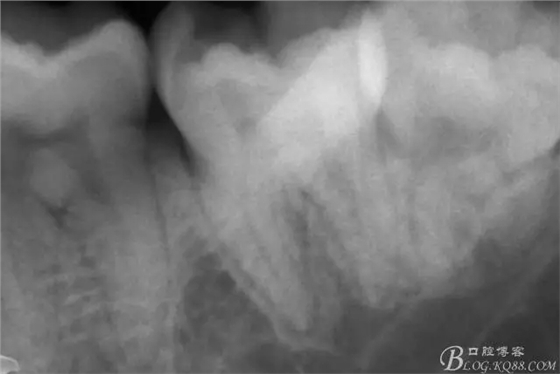

第二次復(fù)診,37叩(+-)。去除暫封物,沖洗,8號~12號挫疏通根管,15號挫用VDW電測確定根管工作長度,M :18mm D :18mm,對應(yīng)洞緣為標(biāo)記點(diǎn)。其中近中根管感覺是頰舌兩根管,但進(jìn)針感覺又是一根管,運(yùn)用Crown Down Technique預(yù)備法,M3挫登士柏機(jī)動(dòng)配合EDTA,1%次氯酸鈉,生理鹽水交替沖洗。紙尖干燥,封氫氧化鈣。